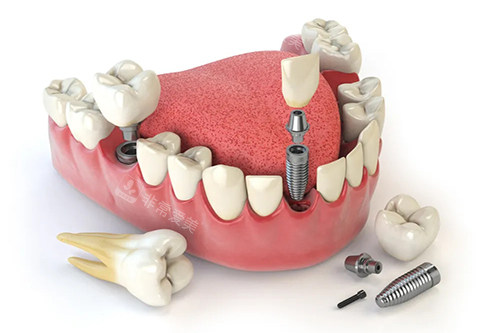

牙齿种植卡通示意图

他们不断学习和掌握国内外新型的口腔医学技术,能够熟练开展各类口腔诊疗项目,如牙齿种植、牙齿矫正、口腔修复、牙周治疗等,为患者提供高质量的口腔医疗服务。